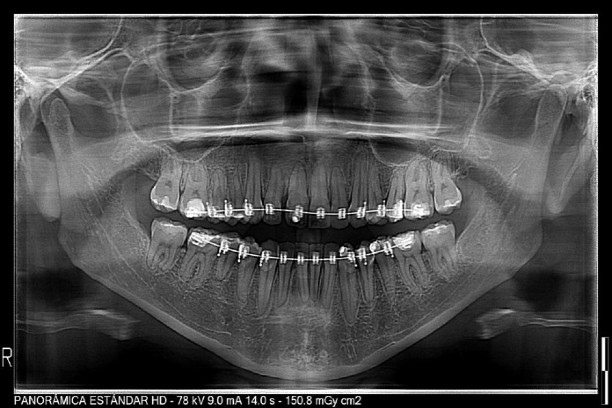

Ofrecemos exámenes de imagenologia 2D y 3D de gran calidad con informes certeros para complementar su diagnóstico clínico, tratamiento y prevención de enfermedades en el área de odontología